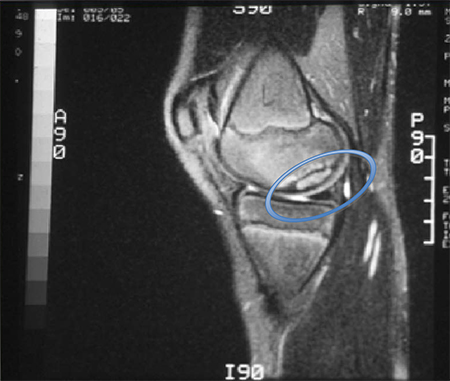

Sagittal magnetic resonance image (MRI) of the talus, showing an osteochondral lesion on the posterior aspect of the talar dome

Gupta RK, Kansay R, Aggarwal V, et al. Osteochondritis dessicans of the talus in a 26-year-old woman. BMJ Case Reports 2009; doi:10.1136/bcr.06.2008.0091